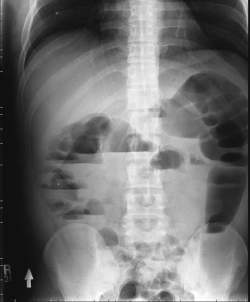

Volvulus

Bowel Obstruction

Twisting of any part of the bowel @ its mesenteric attachment site

MC Sigmoid Colon & cecum

Sxs - obstruction

Dx - KUB series

Tx -

Large Bowel Obstruction

Causes - volvulus, adhesions, hernias, colon cancer (MCC in elderly ppl)

Dx: